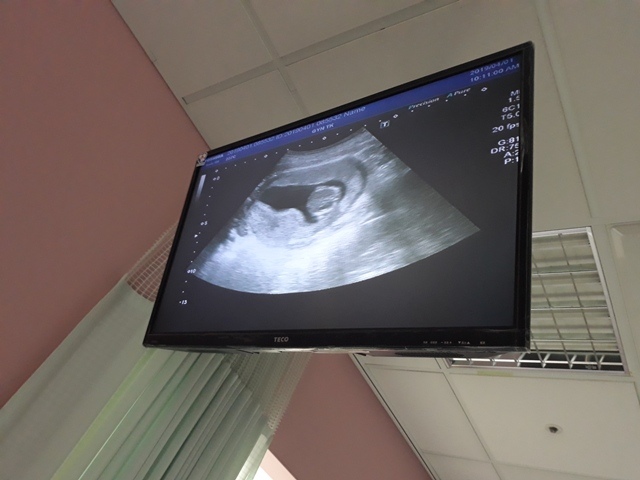

當小純進入診間看診時,我並沒有進去,因為小純說,有時男生不能進去,會被請出來。在外頭等待的我感到很緊張,不久之後,謢理人員請我進入診間,我嚇了一跳,想說發生什麼事了,進入之後,得知小純真的懷孕了,而且已懷了九星期又五天。看診的醫師說,驗孕棒第二條線淡淡的,沒想到胚胎照出來那麼大了,說Baby很健康。還說一閃一閃的是他的心跳,有頭、有手、有腳還有臍帶。小純後來說看了內心覺得很感動,才叫我一起進去看。

小純肚子裡的Baby超音波圖↓